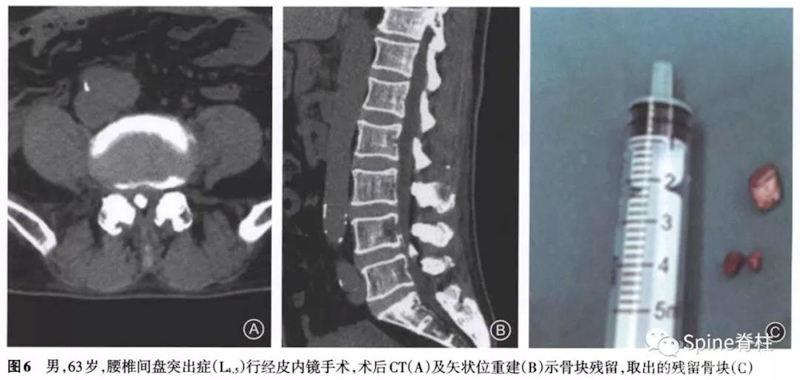

所有7例患者在经皮内镜手术中均进行了椎间孔成形操作。5例为术后立即出现症状,1例为术后1周出现症状,1例为术后1个月出现症状。经保守治疗后,1例患者症状好转拒绝手术,2例出现对侧的刺激症状,余4例均为原症状加重。其中因残留骨块刺破硬膜囊出现脑脊液漏者2例,残留骨块损伤神经引起下肢肌力下降1例。术后CT提示5例骨块在椎问孔成形同侧,2例在对侧。

术后至翻修时间最短为2d,最长为3个月。翻修术式:2例为椎间盘镜手术,1例为可动式椎间盘镜手术,1例为小切口开窗减压术,1例为经皮内镜手术,1例为微创经椎间孔入路腰椎椎体间融合术。